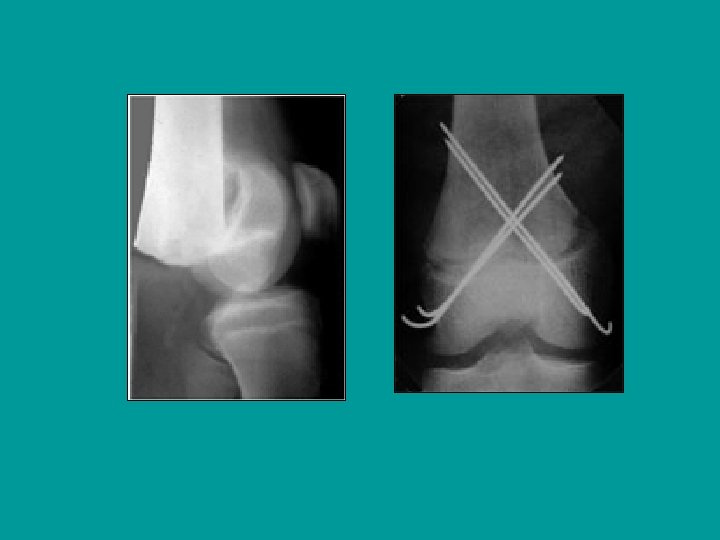

12 años: traumatismo en hiperextensión de la rodilla Salter-Harris tipo I, muy desplazada

Reducción de los desplazamientos en hiperextensión Tracción en el eje de la pierna, con la rodilla en flexión, mientras que reposicionamos la epífisis presionando hacia atrás y distal +/- corrección lateral

Enclavijado percutáneo

Salter-Harris tipo I, muy desplazada: reducción y enclavijado percutáneo